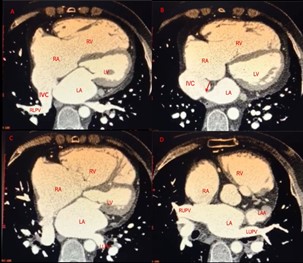

Rezidu defekt varlığında parsiyel pulmoner venoz dönüş anomalisi eÅŸliÄŸini sorgulamak amacıyla ileri tetkik olarak kardiyak bilgisayarlı tomografi istendi. Görüntülemede; Resim-7’de A sekmesinde gösterilen kesitlerde saÄŸ alt pulmoner venin IVC’ye drene olduÄŸunu görebilmekteyiz. B sekmesinde ise okla iÅŸaretlenen bölgede IVC tip rezidü ASD’nin sol atriuyuma açılış yeri iÅŸaret edilmektedir. C ve D sekmelerinde ise saÄŸ üst ve sol üst-alt pulmoner venlerin normal biçimde sol atriyuma drenajı gösterilmiÅŸtir.

Resim-7: